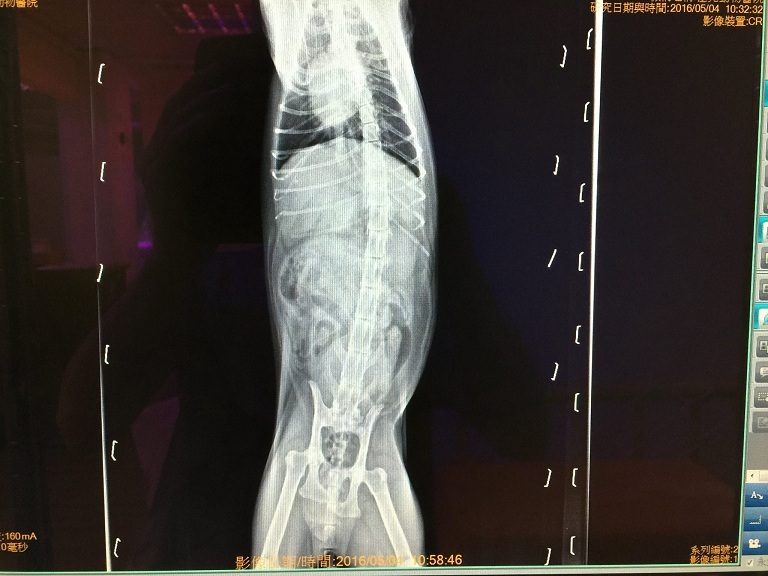

5/4回診- 3.075kg

小八最近有體重大幅下降的情況,

(醫生說正常應該要有3.7、3.8kg)

因此醫生今天做了較詳細的檢查。

而醫生在全身X光照片中發現小八的骨盆有點歪斜,

雖不至於影響食慾、但須留意。